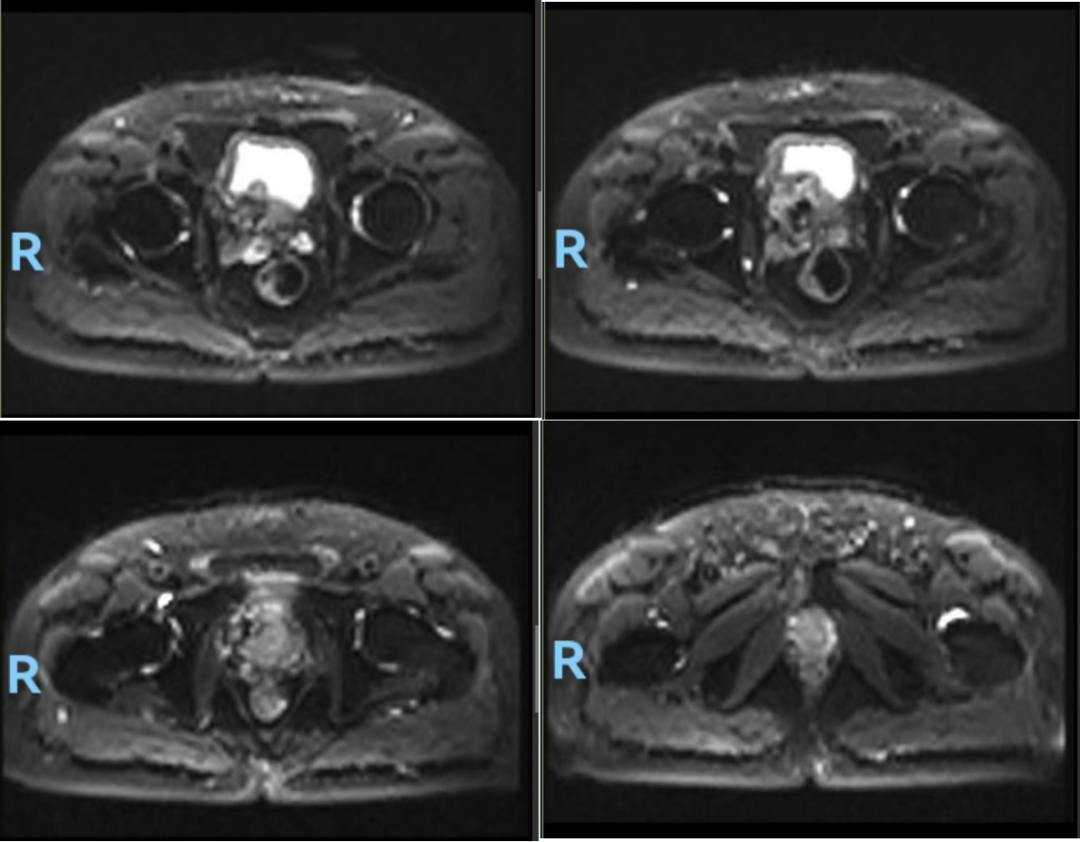

前列腺MR(图1,2024-04-18):1、考虑前列腺癌,PI-RADS 5,膀胱后壁、双侧精囊腺浸润;2、双侧耻骨及第1骶骨异常信号,转移瘤可能。

图1.前列腺MR(2024-04-18):前列腺体积不规则增大,约6.2cm(左右)x5.4cm(前后)x7.1cm(上下),中央带、外周带可见不规则片状短T2等T1信号灶,病灶向上突向膀胱,与膀胱后壁及精囊腺分界不清,DWI示病变呈弥散受限高信号,相应ADC信号减低。盆腔内见多个小淋巴结,较大者短径约为0.6cm。双侧耻骨及第1骶骨见稍长T1长T2信号,DWI弥散受限改变。直肠右侧壁局部增厚。诊断:1、考虑前列腺癌,PI-RADS 5,膀胱后壁、双侧精囊腺浸润;2、双侧耻骨及第1骶骨异常信号,转移瘤可能

图5.复查前列腺MR(2024-09-19):前列腺大小约4.2cmx3.5cmX3.5cm,以中央腺体增大为主,T1WI呈等信号,T2WI呈等、高信号,其中中央腺体前下份局部呈结节状突向膀胱颈,与膀胱后壁分界欠清,DWI扩散受限呈高信号,ADC图呈低信号:双侧外周带可见条片状低信号DWI未见明显高信号。双侧精囊腺大小和形态尚可,压脂像示局部信号减低膀胱精囊角对称。诊断:1、符合前列腺肿瘤治疗后改变2、右耻骨下支异常信号,考虑转移